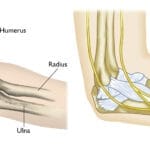

A radiograph of a child’s humerus (arm bone) reveals an aneurysmal bone cyst characterised by bone expansion and a markedly thin outer cortex. Confirming the diagnosis typically requires an MRI scan

X-rays

are typically ordered to evaluate the underlying bone. They commonly reveal a bone lesion altering the bone’s shape and strength, often appearing enlarged with a clear central space and thin cortex.